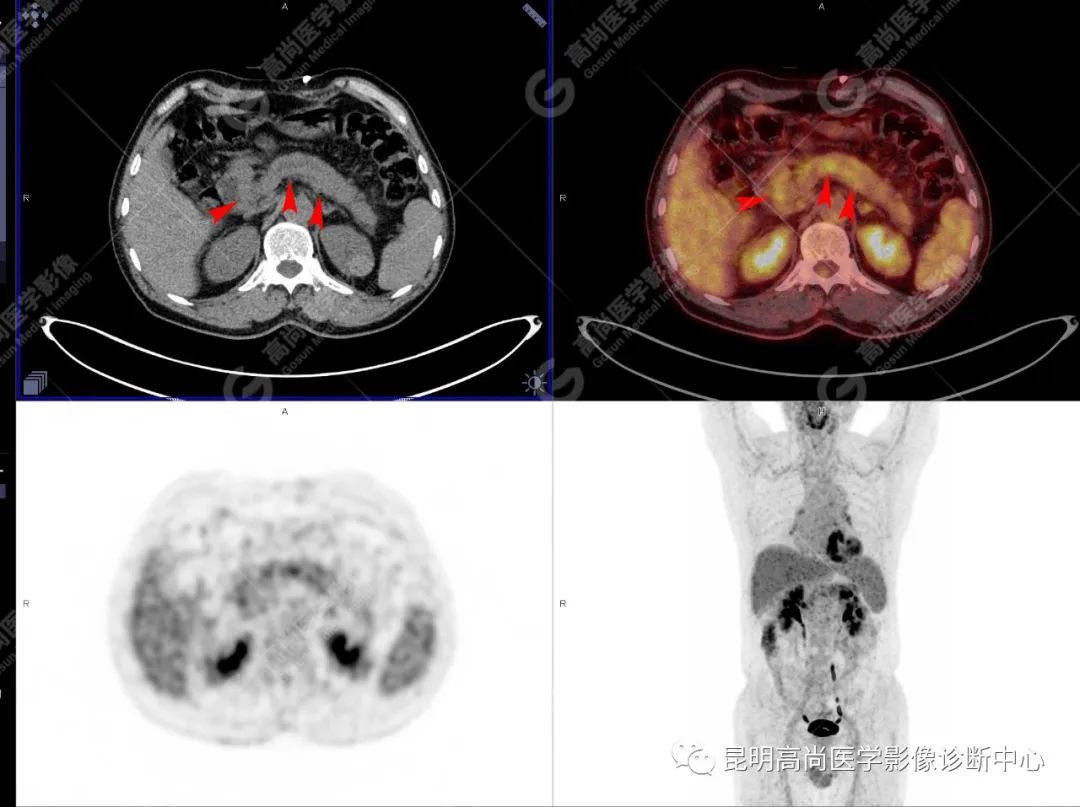

检查图像

影像诊断

十二指肠壶腹区等密度结节影伴糖代谢持续增高,多考虑恶性病变(壶腹癌),继发主胰管扩张及慢性胰腺炎表现;腹膜后多发淋巴结显示,糖代谢不同程度增高,不除外转移。

(1)CT 表现

胰腺局部增大、肿块形成。

胰管阻塞、肿瘤远端的主胰管扩张,甚至形成潴留性囊肿。

胰管、胆总管均受累、扩张,形成「双管征」。

肿瘤侵犯胰腺周围血管及脏器。

增强后强化不明显。

(4)18F-FDG PET/CT

在诊断胰腺癌方面具有较高的敏感性,其敏感性可达 85%~90%,特异性可达 55.6%~94%;尤其在鉴别良恶性的囊性肿瘤时,其准确率可达到 94%~95%;PET/CT 是胰腺癌的主要检查手段,它比常规 CT 和 MRI 更具优势,可早期发现远处转移灶;同时可以作为一个独立的、用于预测胰腺癌生存和无进展生存的独立的指标,即 SUV,代谢肿瘤体积,即 MTV。